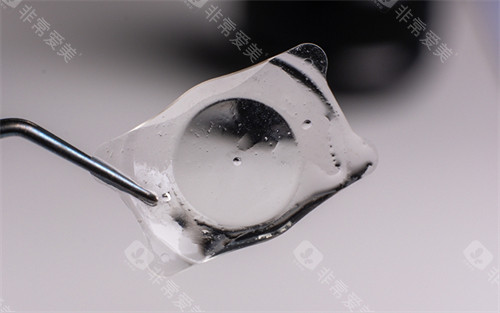

德国人类光学创新“可变光学区”技术,以MCX11ASP型号为例,其光学直径可在4.5-6.0毫米间动态调节。

其专有环形襻结构(如Aspira-aXA型号)通过360度环绕支撑囊袋,植入后稳定性较传统晶体提升显著。

临床数据显示,其单焦点晶体术后囊袋混浊率低于行业均值,这得益于其采用的亲水性丙烯酸酯材料。

该材料表面光滑,可减少蛋白质沉积,同时通过欧盟CE认证,确保长期使用的可靠性。

从原材料筛选到成品出厂,每枚晶体需经历多道检测工序。例如,其亲水性材料需通过模拟人体环境的长期浸泡测试,确保生物相容性。